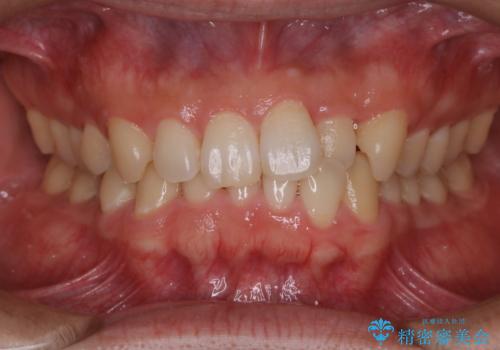

叢生(でこぼこ) 非抜歯、ディスキング(30代女性)

歯を抜かないで、治療しました。

前歯の大きさを0.25ミリずつ、やすりのようなものを使用し、歯のサイズダウンして上下の歯を並べました。